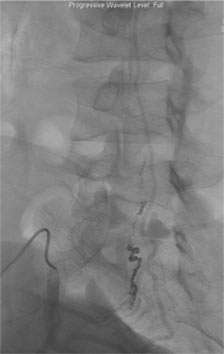

Depending on the lesion, the best treatment plan changes. For intramedullary AVMs, partial or palliative treatment is sometimes an option since complete obliteration may carry a much higher chance of causing neurological deficits than conservative management or partial treatment (Figure 3).

Figure 3: A palliative / partial Catheter Treatment for a Spinal AVM.

Multiple arteries feeding the spinal AVM. There are aneurysms in the feeding arteries.

Two feeding arteries harboring the aneurysms were obliterated using catheter embolization techniques.

The aneurysms were completely obliterated, and the risk of bleeding was reduced. However the AVM receives blood flow from the other feeding arteries.